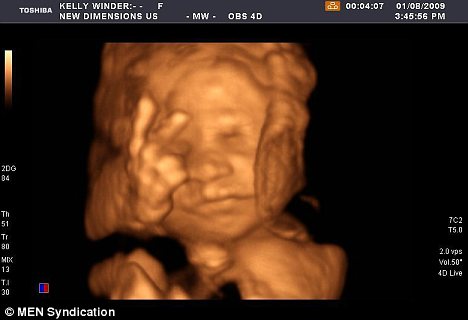

마치 수 개월 뒤에 만날 엄마와 아빠에게 인사를 건네듯, 당당하게 ‘V’자를 그리며 웃고 있는 27주 된 태아의 사진이 인터넷서 화제다.

이제 막 눈·코·입과 손발이 생긴 태아는 매우 편안한 표정으로 몸을 웅크리고 있었다. 놀라운 것은 태아가 고사리 같은 손에서 손가락 두 개를 펼쳐 ‘V‘자를 만든 것.

오웬의 태아 사진은 프레스톤병원에서 큰 관심을 모았다. 병원 측은 오웬 부부의 허락을 구한 뒤 태아의 초음파 사진을 확대해 병원 곳곳에 붙이고, 환자들에게 따뜻한 웃음을 안겨줬다.

네티즌들은 “저 또래 태아들이 활발한 움직임을 보이긴 하지만, 정확히 ‘V’를 그리는 모습을 포착하긴 매우 어렵다.”, “태어나지도 않은 아기가 벌써부터 사랑스럽다.”등의 댓글로 관심을 표시했다.